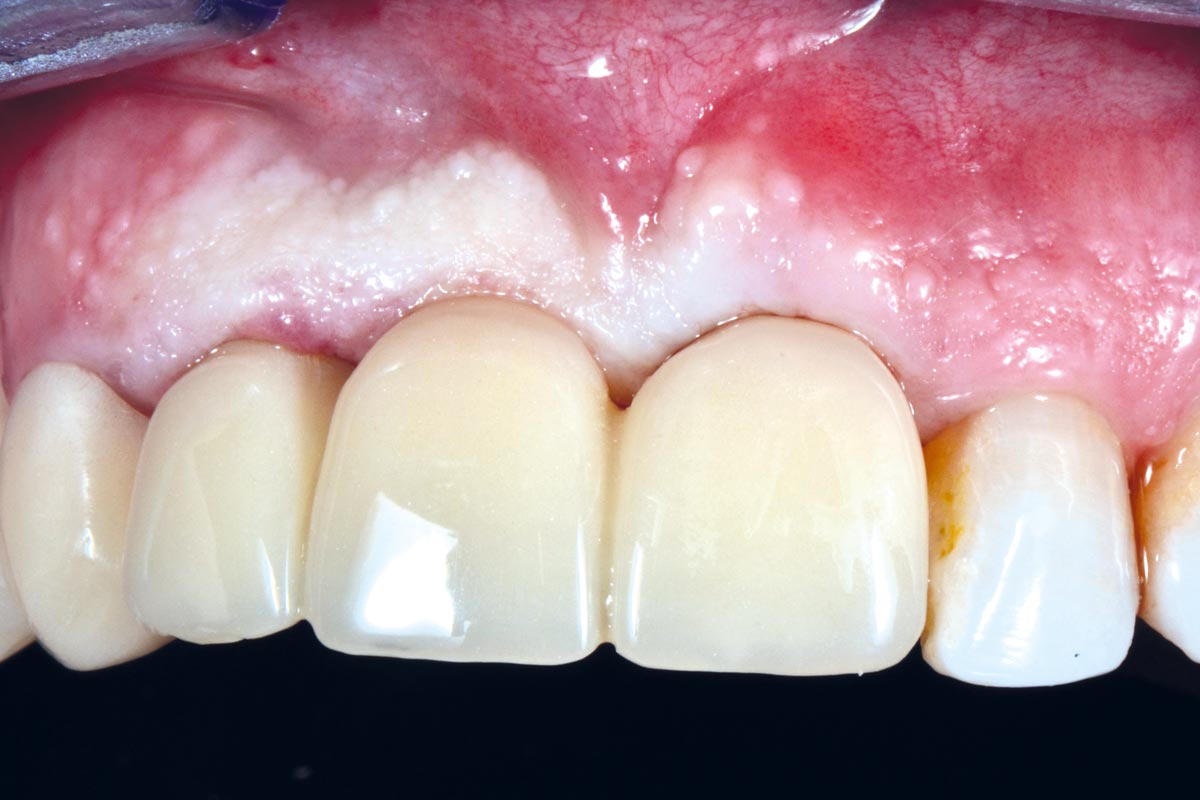

17/17 - Final prosthetic restoration.

Socket preservation using cerabone® and Straumann® Emdogain® - Dr. S. Pelekanos